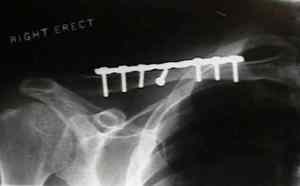

Finalmente llegamos a la cirugía. Quizá el punto más delicado competencia del Traumatólogo-cirujano ortopédico. Si tras aproximadamente 6 meses de tratamiento no obtenemos resultados es cuando optamos por la cirugía. Se dice que hasta un 25% de corredores con esta patología pueden llegar a necesitarla. Y así es. Y personalmente creo que tiene buenos resultados. En mi caso opto por una extirpación del tejido fibrótico o nódulos siempre que el remanente de tendón sea por lo menos del 50%. En el mismo procedimiento se realizan cortes longitudinales sobre el tendón degenerado para , de nuevo, favorecer la vascularización y reparación del tejido afectado.